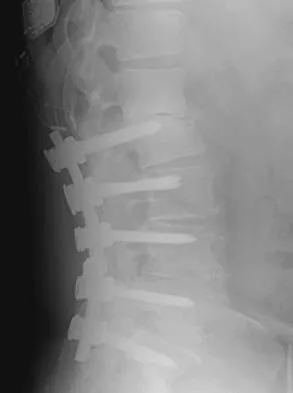

An otherwise healthy 54-year-old man who underwent a successful multilevel lumbar decompression and fusion 4 years ago now reports increasingly severe bilateral thigh claudication with paresthesia and severe back pain for the past 12 months. Physical therapy, bracing, and epidural steroids have failed to provide relief. A radiograph and MRI scans are shown in Figures 15a through 15c. He is afebrile, and laboratory studies show an erythrocyte sedimentation rate of 5 mm/h and a normal WBC count. What is the best course of action?

Detailed Explanation